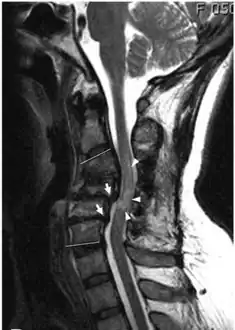

MRI shows retrolisthesis arrows ( and signal change at C3-C5 arrow heads) -

Retrolisthesis of L5-S1